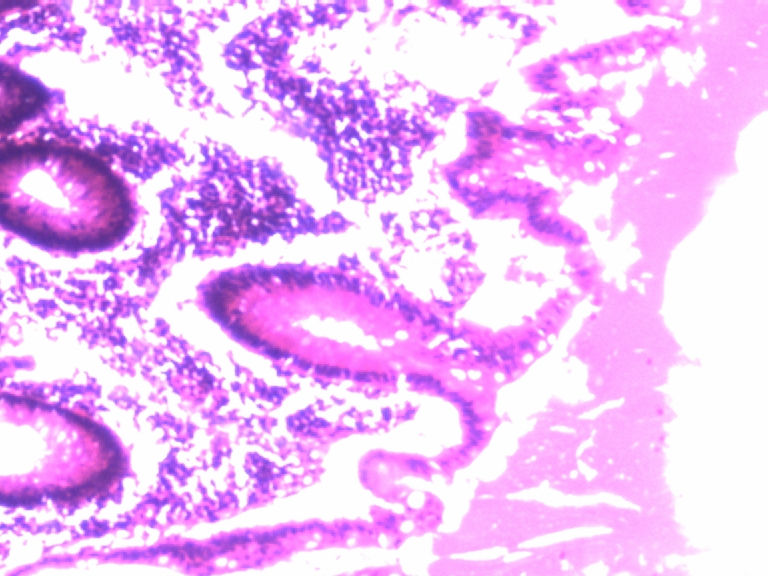

男,50岁,阑尾长7厘米,直径0.4---0.6厘米。剖开:尖端看见淡黄色区,不规则,界限欠清,0.15*0.2厘米,质中。

考虑阑尾类癌

切片不清晰,要考虑阑尾类癌。

倾向神经内分泌肿瘤,建议做CgA、SYN、Ki-67检查。

阑尾的神经内分泌肿瘤我们已经碰到好几例了,一般都在阑尾尖端,取材一定要规范,这样可以减少漏诊率。

按照胃肠胰腺神经内分泌肿瘤WHO2010分类,该例应属于NET G1(神经内分泌瘤,1级)。需标记Syn, CgA, Ki67.